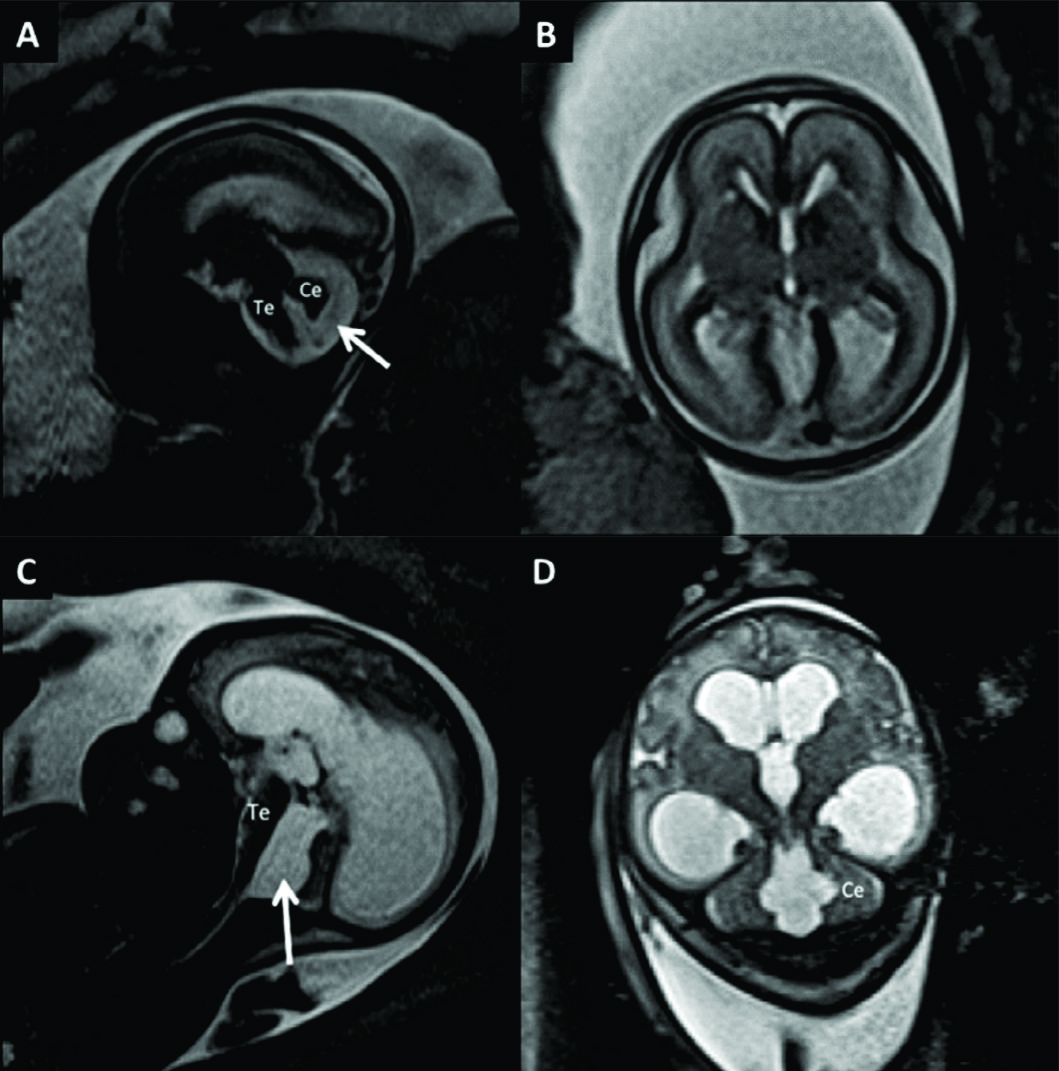

Figura 6

RM Fetal Agenesia del Cuerpo Calloso.

Estudio realizado a las 27 semanas de edad gestacional con diagnóstico de agenesia del CC. En imagen sagital (A) no se observa el CC ni la cisura pericallosa. Los gyrus de la cara mesial toman un aspecto radiado como suele observarse en esta entidad. Los ventrículos laterales (è) toman un aspecto colpocefálico de dirección ántero posterior como se ve en el corte axial (B).

Las estructuras de la fosa posterior son normales. Te: Tronco encefálico Ce: Cerebelo

Figura 9

RM Fetal en Malformación de Fosa Posterior.

Se presentan 2 casos con diagnóstico de Dandy-Walker, ambos con malformación quística de la fosa posterior (è) comunicada con el IV ventrículo por alteración del desarrollo del vermis cerebeloso. En A y B imágenes sagital y axial de RMf realizada a las 27 semanas donde además se identifica dilatación del sistema ventricular supra-tentorial moderada. En el 2º caso (C y D) se observa una severa dilatación del sistema ventricular supra-tentorial con adelgazamiento del cuerpo calloso en un feto de 29 semanas de edad gestacional.

Te: Tronco encefálico

Ce: Cerebelo

Figura 10

RM Fetal en Malformación de Chiari.

Estudio realizado a las 29 semanas con diagnóstico ecográfico de mielomeningocele. En imagen coronal (A) se observa la severa dilatación del sistema ventricular supra-tentorial lo que se corrobora en la imagen axial (B) con una disposición colpocefálica de los ventrículos laterales (VL). En la imagen fetal sagital (C) se reconocen el cerebelo (Ce) y tronco encefálico (Te) sin identificarse claramente el IV ventrículo lo que indica una disminución de las dimensiones de la fosa posterior. En el mismo plano se observa el defecto de cierre posterior del tubo neural (è) con un saco de meningocele. La imagen axial a nivel de ese saco (D) muestra claramente el defecto espinal posterior (è) aunque sin observarse claramente el contenido neural del mismo.